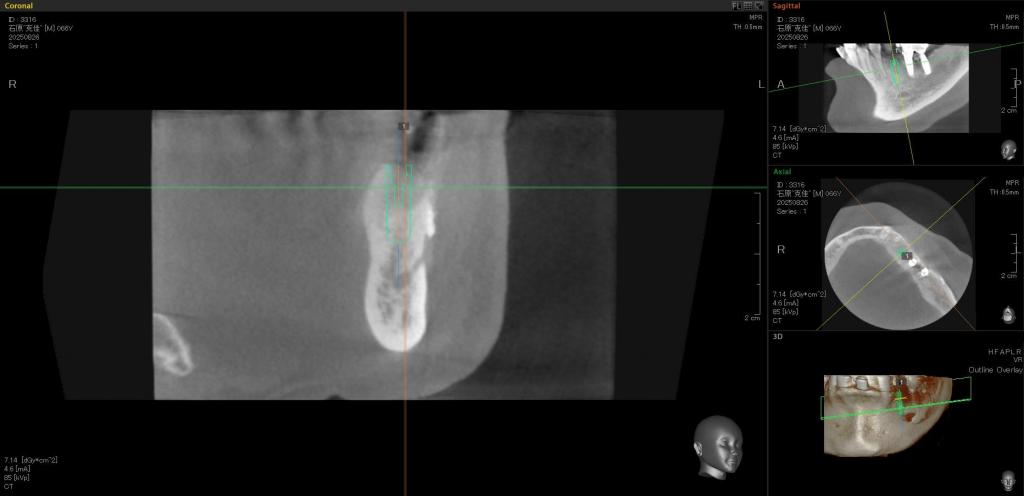

治療中写真

- 「インプラントで修復できないか?」と言うことで、CTを撮影し、手術を行いました。

- 適切な位置に埋入しました。